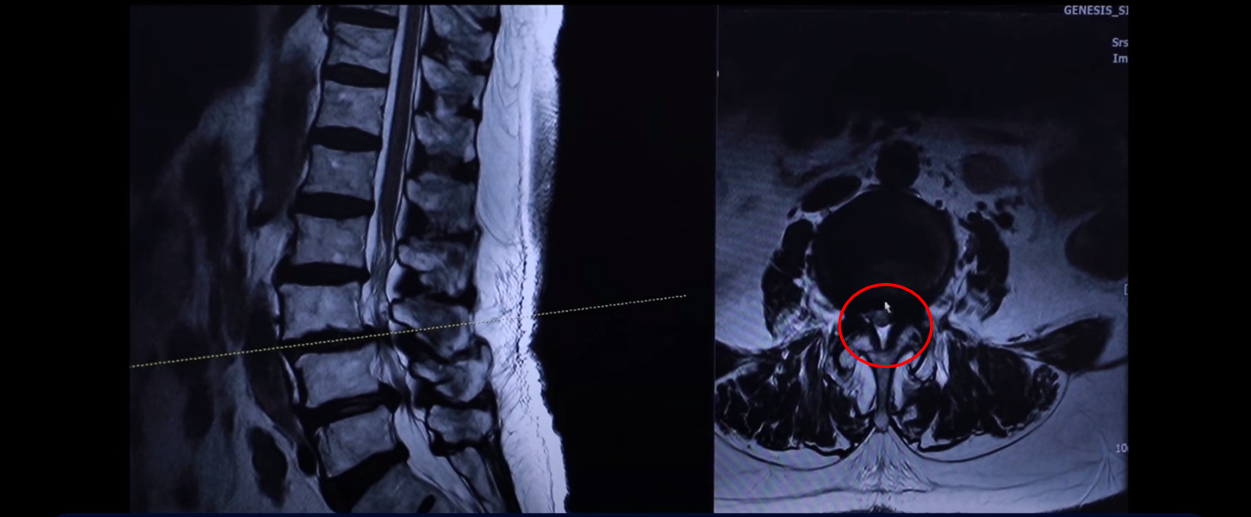

이분 근육 상태를 이 MRI에서 볼 수 있는 부분이 있습니다. 특히 이 하부 요추 5번 1번에서 보시면 이게 허리를 펴주는 기립근이라는 근육입니다.

이 근육을 보시면 왼쪽 화면에 정상적인 기립근의 모양을 비교 해보시면 이런 데가 정상적인 근육은 까맣게 보여야 됩니다. 그게 정상적인 근육인데 보시면 하얗게 변해 있죠. 이게 지방으로 변해버린 겁니다.

이렇게 지방으로 변해버리면 힘을 못 씁니다. 그래서 허리를 펴기도 어렵고 허리를 지탱하기도 어려운 거죠.

그 다음에 이게 장요근인데 이분은 아주 나빠 보이시지 않는데 그렇다고 좋은 것도 아닙니다.

또 정상적인 장요근을 이 왼쪽에 보여드릴 텐데 한번 비교해 보시면

크기나 밀려나간 모양 또 이렇게 앞으로 밀려나갈수록 허리도 많이 구부러져 있다 이렇게 보시면 됩니다.

그래서 이렇게 근육 상태가 어떤지 이렇게 객관적으로 볼 수 있는 부분도 MRI에서 보실 수 있습니다. 그만큼 근육이 안 좋아지니까 나이가 드시면서 또 이런 근육들이 뭉쳐 있고 굳어 있고 또 기능을 잘 못하게 되니까 또 근육 자체도 뭉쳐 있으면 아픕니다. 그러니까 허리를 잘 지탱하지 못하니까 이런 신경 구멍이 좁아진 곳에서 신경이 눌리는 겁니다. 허리를 잘 지탱할 수 있도록 근육 기능들을 살려주니까 훨씬 더 신경 눌림이 덜해지고 힘을 잘 쓸 수 있고 더 잘 걷게 되는 겁니다.